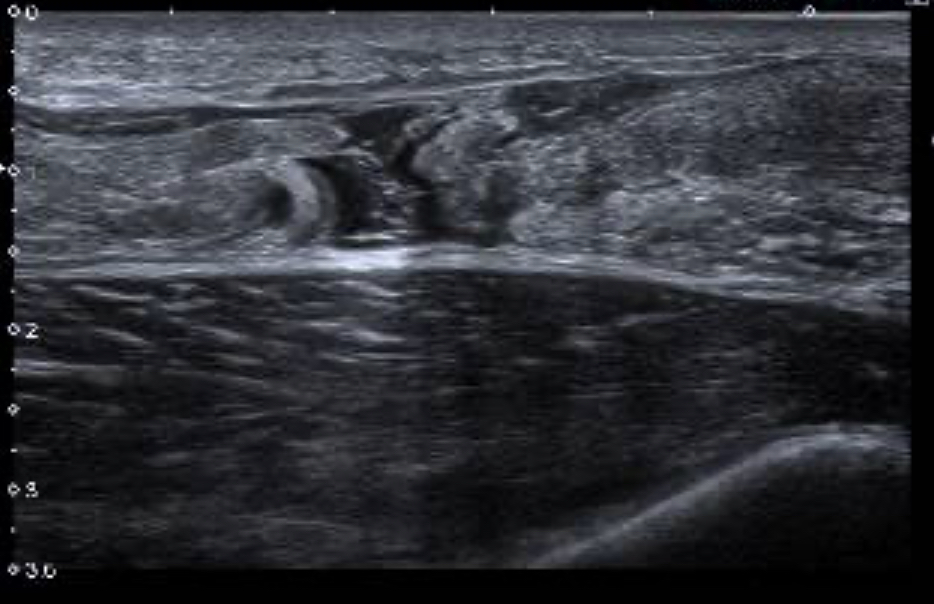

En la primera imagen en corte longitudinal se aprecia una imagen hipoecogénica correspondiente a rotura completa del tendón de Aquiles, limitada por dos estructuras hiperecogénicas que corresponden con los cabos proximal y distal del tendón de Aquiles.